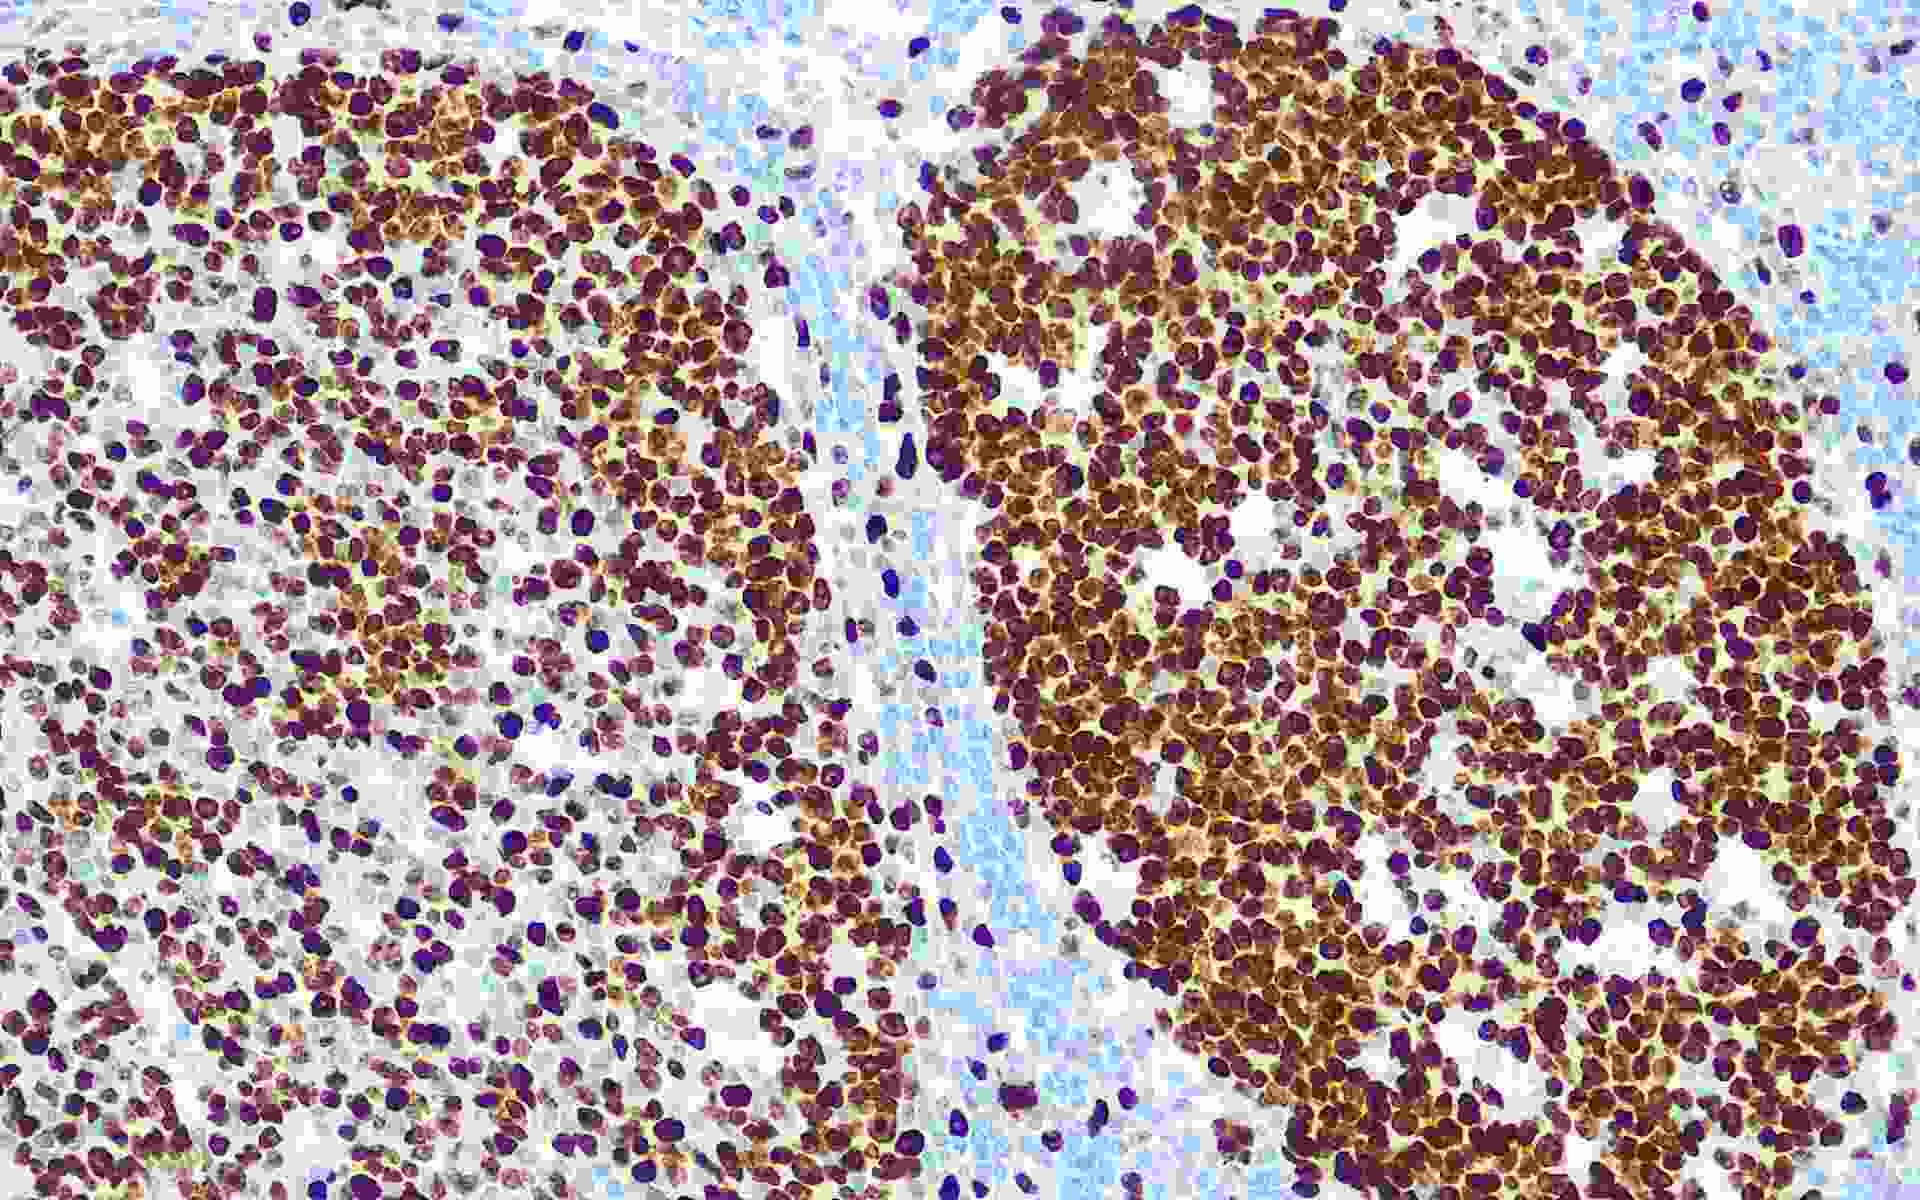

Ki-67抗原是一種與細(xì)胞增殖特異相關(guān)的核抗原,主要用于研究細(xì)胞增殖活性。Ki-67在所有細(xì)胞周期活動期(G1晚期、S、G2和M期)的增殖細(xì)胞中表達(dá),但在靜止細(xì)胞中不表達(dá)。G1期它在核仁外周區(qū)占優(yōu)勢,在稍后時期也出現(xiàn)在核基質(zhì)。Ki-67被認(rèn)為涉及細(xì)胞增殖的維持,然而,其發(fā)揮功能的機(jī)制尚未清楚。資料表明Ki-67增殖指數(shù)高低與腫瘤的分化程度、浸潤轉(zhuǎn)移以及預(yù)后密切相關(guān)。所以在腫瘤的研究中是一種重要的參考依據(jù)。